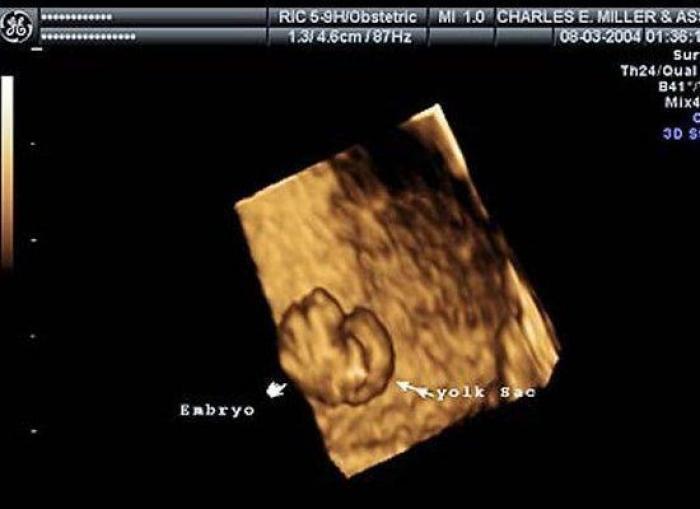

En esta galería puedes ver en fotos como es el desarrollo de un feto de semana en semana:

Desarrollo del feto, en fotos

Ver la galería